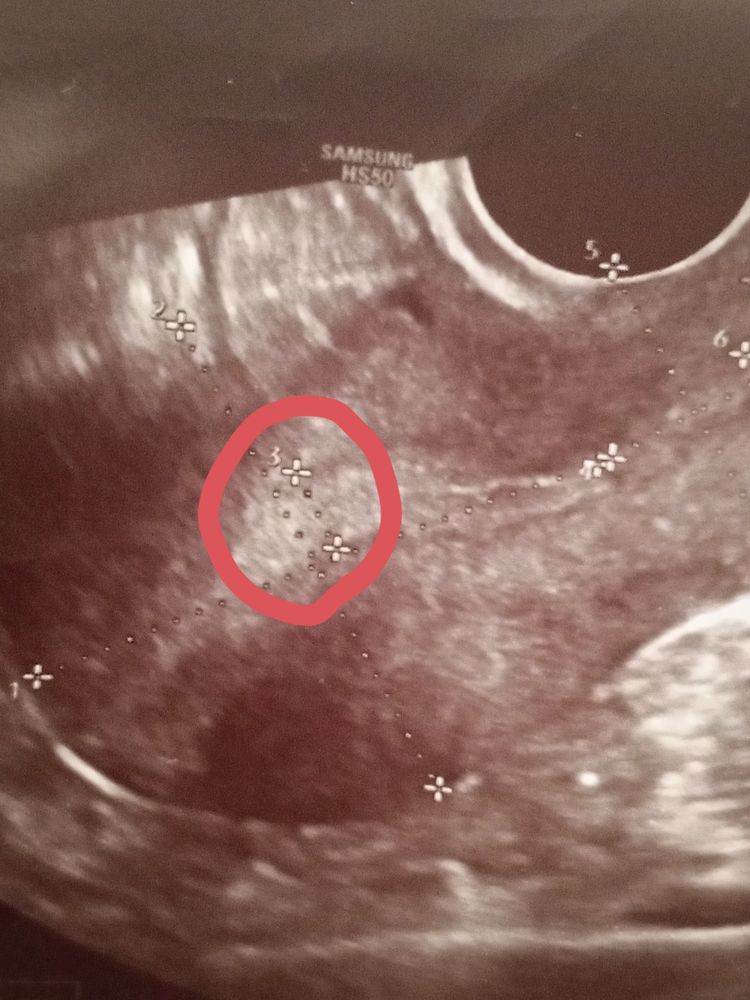

Светлана , вот смотрите первая и вторая фаза, мне кажется у вас не было овуляции и эндометрий на 1 фазу, т.к. видно линию смыкания, но я не узист конечно, просто уже за кучу узи у себя различаю Изображение Изображение

Аня, вот это как я понимаю эндометрий или нет? Изображение

Светлана , вот у вас эндометрий, слева это ближе ко дну матки, а справа к шейке Изображение